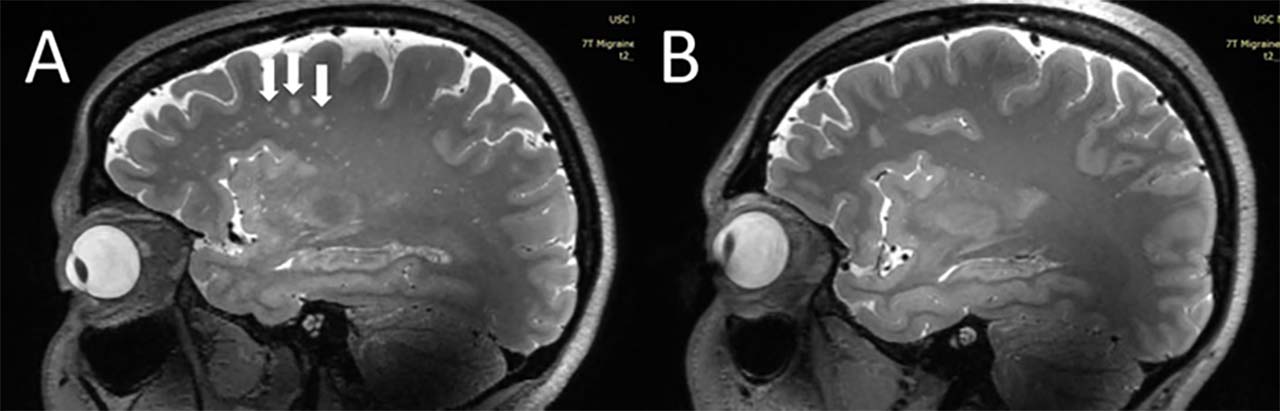

Solda: Migrene sahip kişiye ait MRI - Sağda Migrensiz kişiye ait MRI:

Güney Kaliforniya Üniversitesi’nden bilim insanları, migrene sahip kişilerin beynindeki değişilikleri görüntüledi. Kronik ve aurasız epizodik migrenli kişilerde, ‘centrum semiovale’ adı verilen beyin bölgesinin mikroskobik boyuttaki perivasküler boşluklarının büyüdüğü gözlemlendi.

Perivasküler boşluk olarak tanımlanan alan, beyindeki kan damarlarını çevreleyen sıvı boşluklardan oluşuyor. Bu boşluklar, özellikle kan-beyin bariyerindeki anormallikler ve iltihap gibi durumlardan etkileniyor.